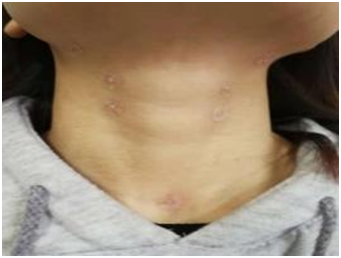

(3)揿针:局部取人迎、水突、廉泉、开音1号、开音2号等穴;远端取合谷、足三里、三阴交、太冲等穴。

揿针治疗 推拿按摩